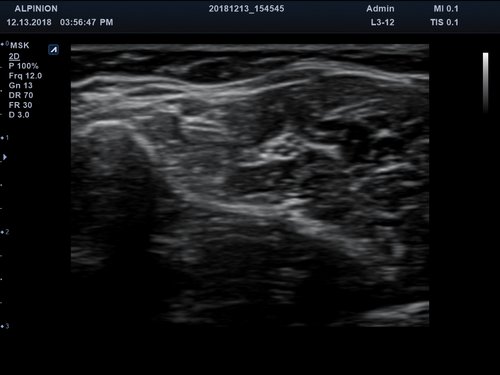

Eigenschaft minisono C1-6 minisono L3-12

Typ konvex linear

Frequenz 1 - 6 MHz 3 - 12 MHz

Maße (Länge/ Breite/ Höhe) 25,5/ 62,5/ 157mm 25,2/ 62,5/ 150mm

Gewicht 5,8 oz/ 175g 5,6 oz/ 165 g

Scan-Tiefe 30 cm 10 cm

Sichtfeld 78 ° 38,4 mm

Display Microsoft Surface Microsoft Surface

Batterielaufzeit 300 min 300 min

Anwendungsbereiche Abdomen MSK, Nerven, Karotis, periphere Gefäße, Schilddrüse, Mamma

Bildgebungs-Modi B-Modus, CF, M, PW, PD B-Modus, CF, M, PW, PD

Das minisono-Ultraschallsystem ist mit folgenden Technologien ausgestattet:

• B-Modus: Darstellung zweidimensionale Bilder anatomischer Strukturen

• PW-Doppler (Pulsed-Wave): Verfahren, das ein Geschwindigkeitsspektrum von beweglichem Gewebe und Flüssigkeiten an einer bestimmten Position liefert

• Farbdoppler: farbige Darstellung der Richtung des Blutflusses

• Speckle Reduction Imaging: Basisfilter zur Verbesserung der Bildqualität

• Advanced Speckle Reduction Imaging: Filtertechnologie zur Minimierung der Artefakte und Verbesserung der Definition der Gewebegrenzen

• Filtered Tissue Harmonic Imaging: Bilder mit verbesserter Kontrastauflösung und deutlich reduziertem Rauschen durch Analyse der harmonischen Oberwellen

• Spatial Compounding Imaging: Technologie, die durch mehrere, kombinierte Abstrahlwinkel höhere Kontraste, weniger Artefakte und homogene Aufnahmen vom Nah- bis zum Fernfeld bietet